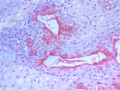

Macroscopic finding:A well-demarcated solid tumor lies in the parotid gland. The cut surface of this tumor is yellowish-white with focal glistening areas. The glistening areas correspond to abundant myxomatous or chondroid stroma.